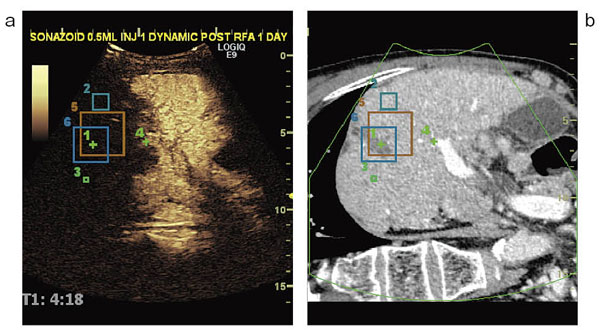

また,GPSは,正確な三次元情報を元にマーキングした位置を,常にトラッキングしてナビゲーションする機能である。図5は,bが過去のCT画像,aが現在のソナゾイド造影超音波画像だが,ターゲットの中心が+で表示され,また,マージンをとる位置が□で表示されている。この□の大きさは,マークした位置から離れるほど大きくなるため,企図したマージンと実際の焼灼位置との関係がわかりやすく,三次元的なセーフティマージンの評価が可能で,追加治療にも有用である。

図5 Volume NavigationのGPS機能